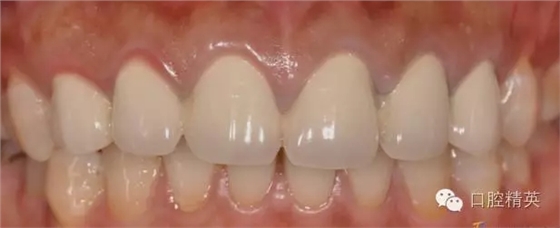

修復(fù)體完成口內(nèi)照片

640.webp (20).jpg

640.webp (21).jpg